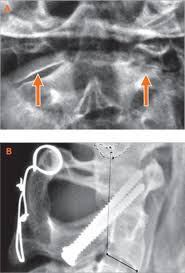

Spondylose Symptome Diagnose Therapie Reha

Spondylose Symptome Diagnose Therapie Reha from www.qualitaetskliniken.de. Klick hier um mehr zu erfahren!